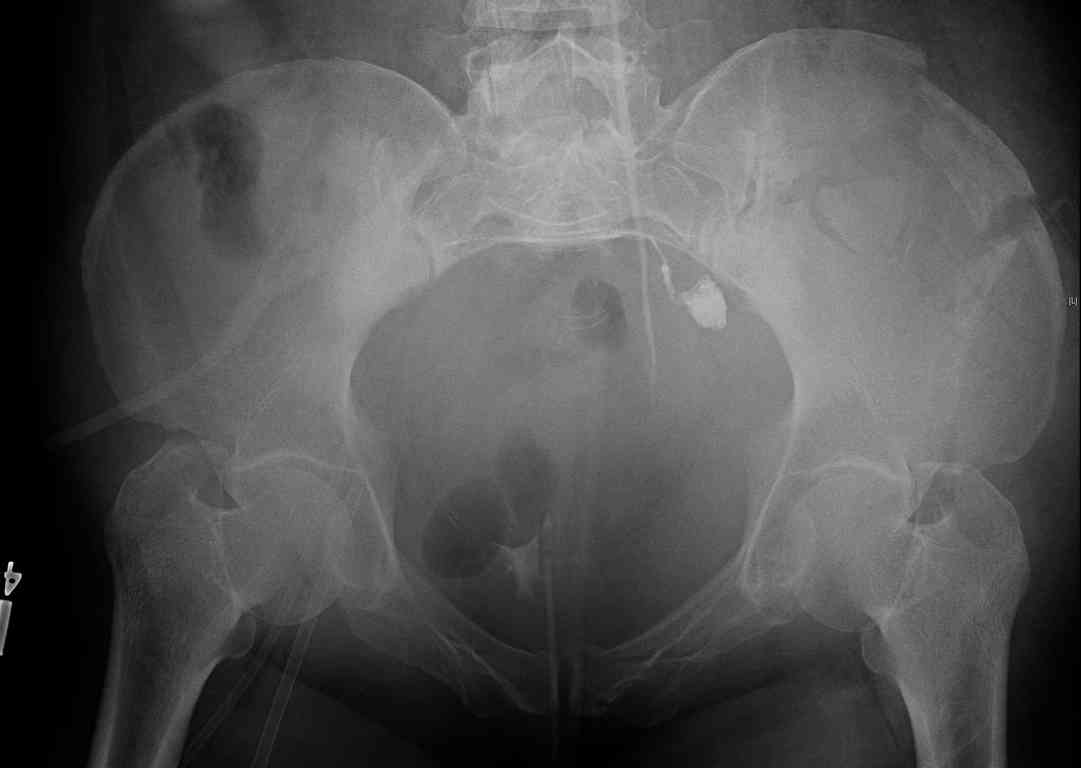

comminuted crescent fx

40 ish female ejected from car. Unstable, DPL negative, went to angio and had her pelvic bleeds embolized after many units of blood. GCS 6, floating elbow, clavicle, bothbones, etc.

My standard approach to this pelvis would be posterior, reduce/lag/plate thecrest, reduce/plate the caudal extent on the posterior crest and 1-2 lags back to front. In this case, the crest comminution seems to make plating all the way to the ASIS useless, as the plate would be on free floating fragments. Would plating the posterior extent of the fracture to secure the reduction at the SI joint and 2 screws back to front be sufficient fixation? Would anyone do a perc reduction and perc back to front screws, and would that be sufficient if the SI joint could be reduced (although I don't see how this could be accurately reduced closed). Would an ilioninguinal with a pelvic brim plate and posterior column screws be a better approach, although reducing the SI would be more indirect and less accurate?

It's a comminuted iliac fracture involving the GS notch and all that

implies...use the lateral interval of an ilioinguinal, sequentially reduce,

and fix...if you want to, you can attach the dominant unstable fragment to

both the stable posterior iliac fragment and also to the anterolateral portion of the sacrum using plates...if you choose to anchor to both, the implants get congested on the iliac side of the SI joint so be precise with contouring and such applications...perhaps and based on the images shown, an iliosacral screw would only augment the construct if applied to the second sacral segment (but this is difficult to assess on the images shown). The crest components can be held securely with screws and/or peripheral plating.

I always manage these percutaneously. The basic idea is to peg the AIIS fragment to the crescent frag still attached to the sacrum.

But the reported results of open treatment are very good, so your plan of ORIF should yield acceptable results.